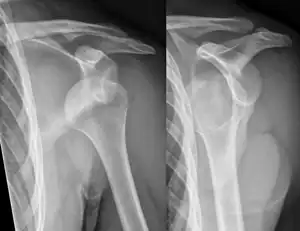

An anterior dislocation of the shoulder

Anterior dislocation of the right shoulder. AP X ray

Anterior dislocation of the right shoulder. Y view X ray.